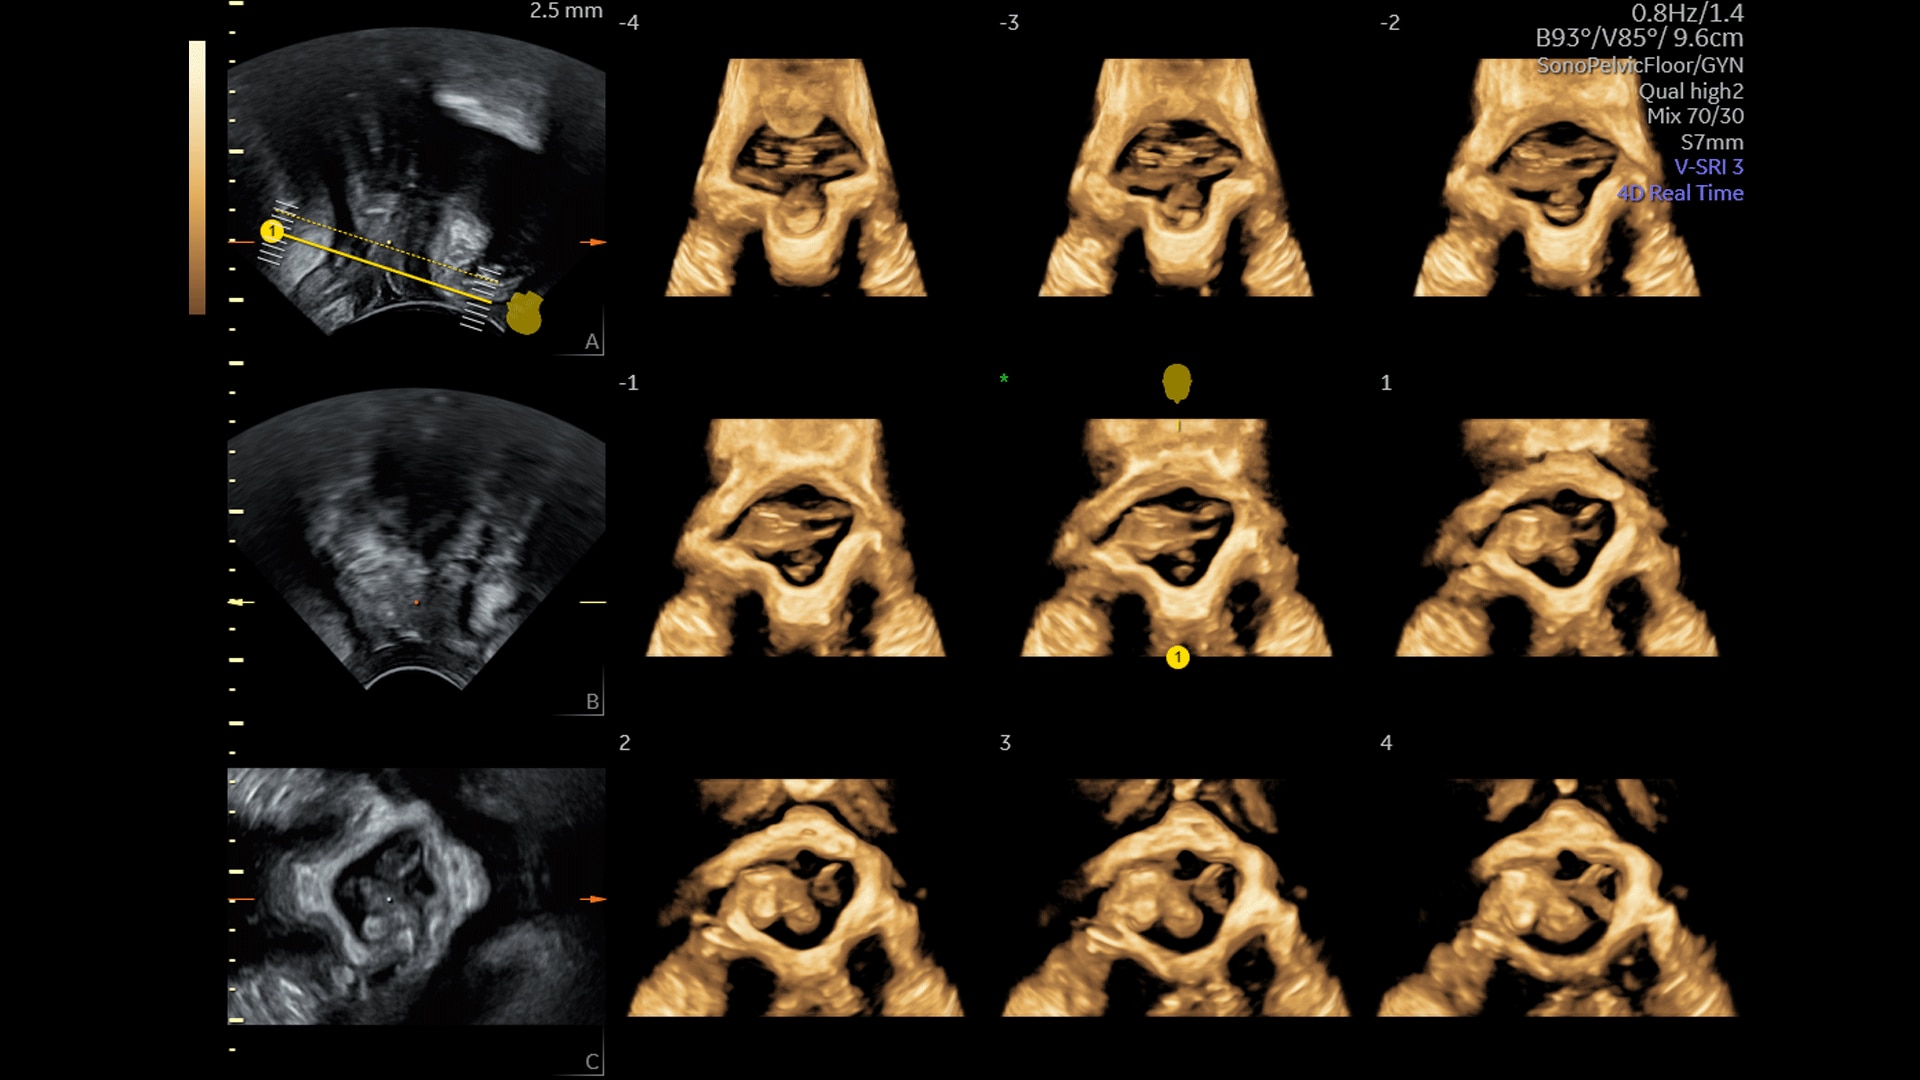

Amplify imaging performance and simplify scanning with our most advanced architecture

Extraordinary clarity and definition so you can focus on early detection and intervention.

Save time, steps, and effort by leveraging AI, automation tools, and ergonomic design